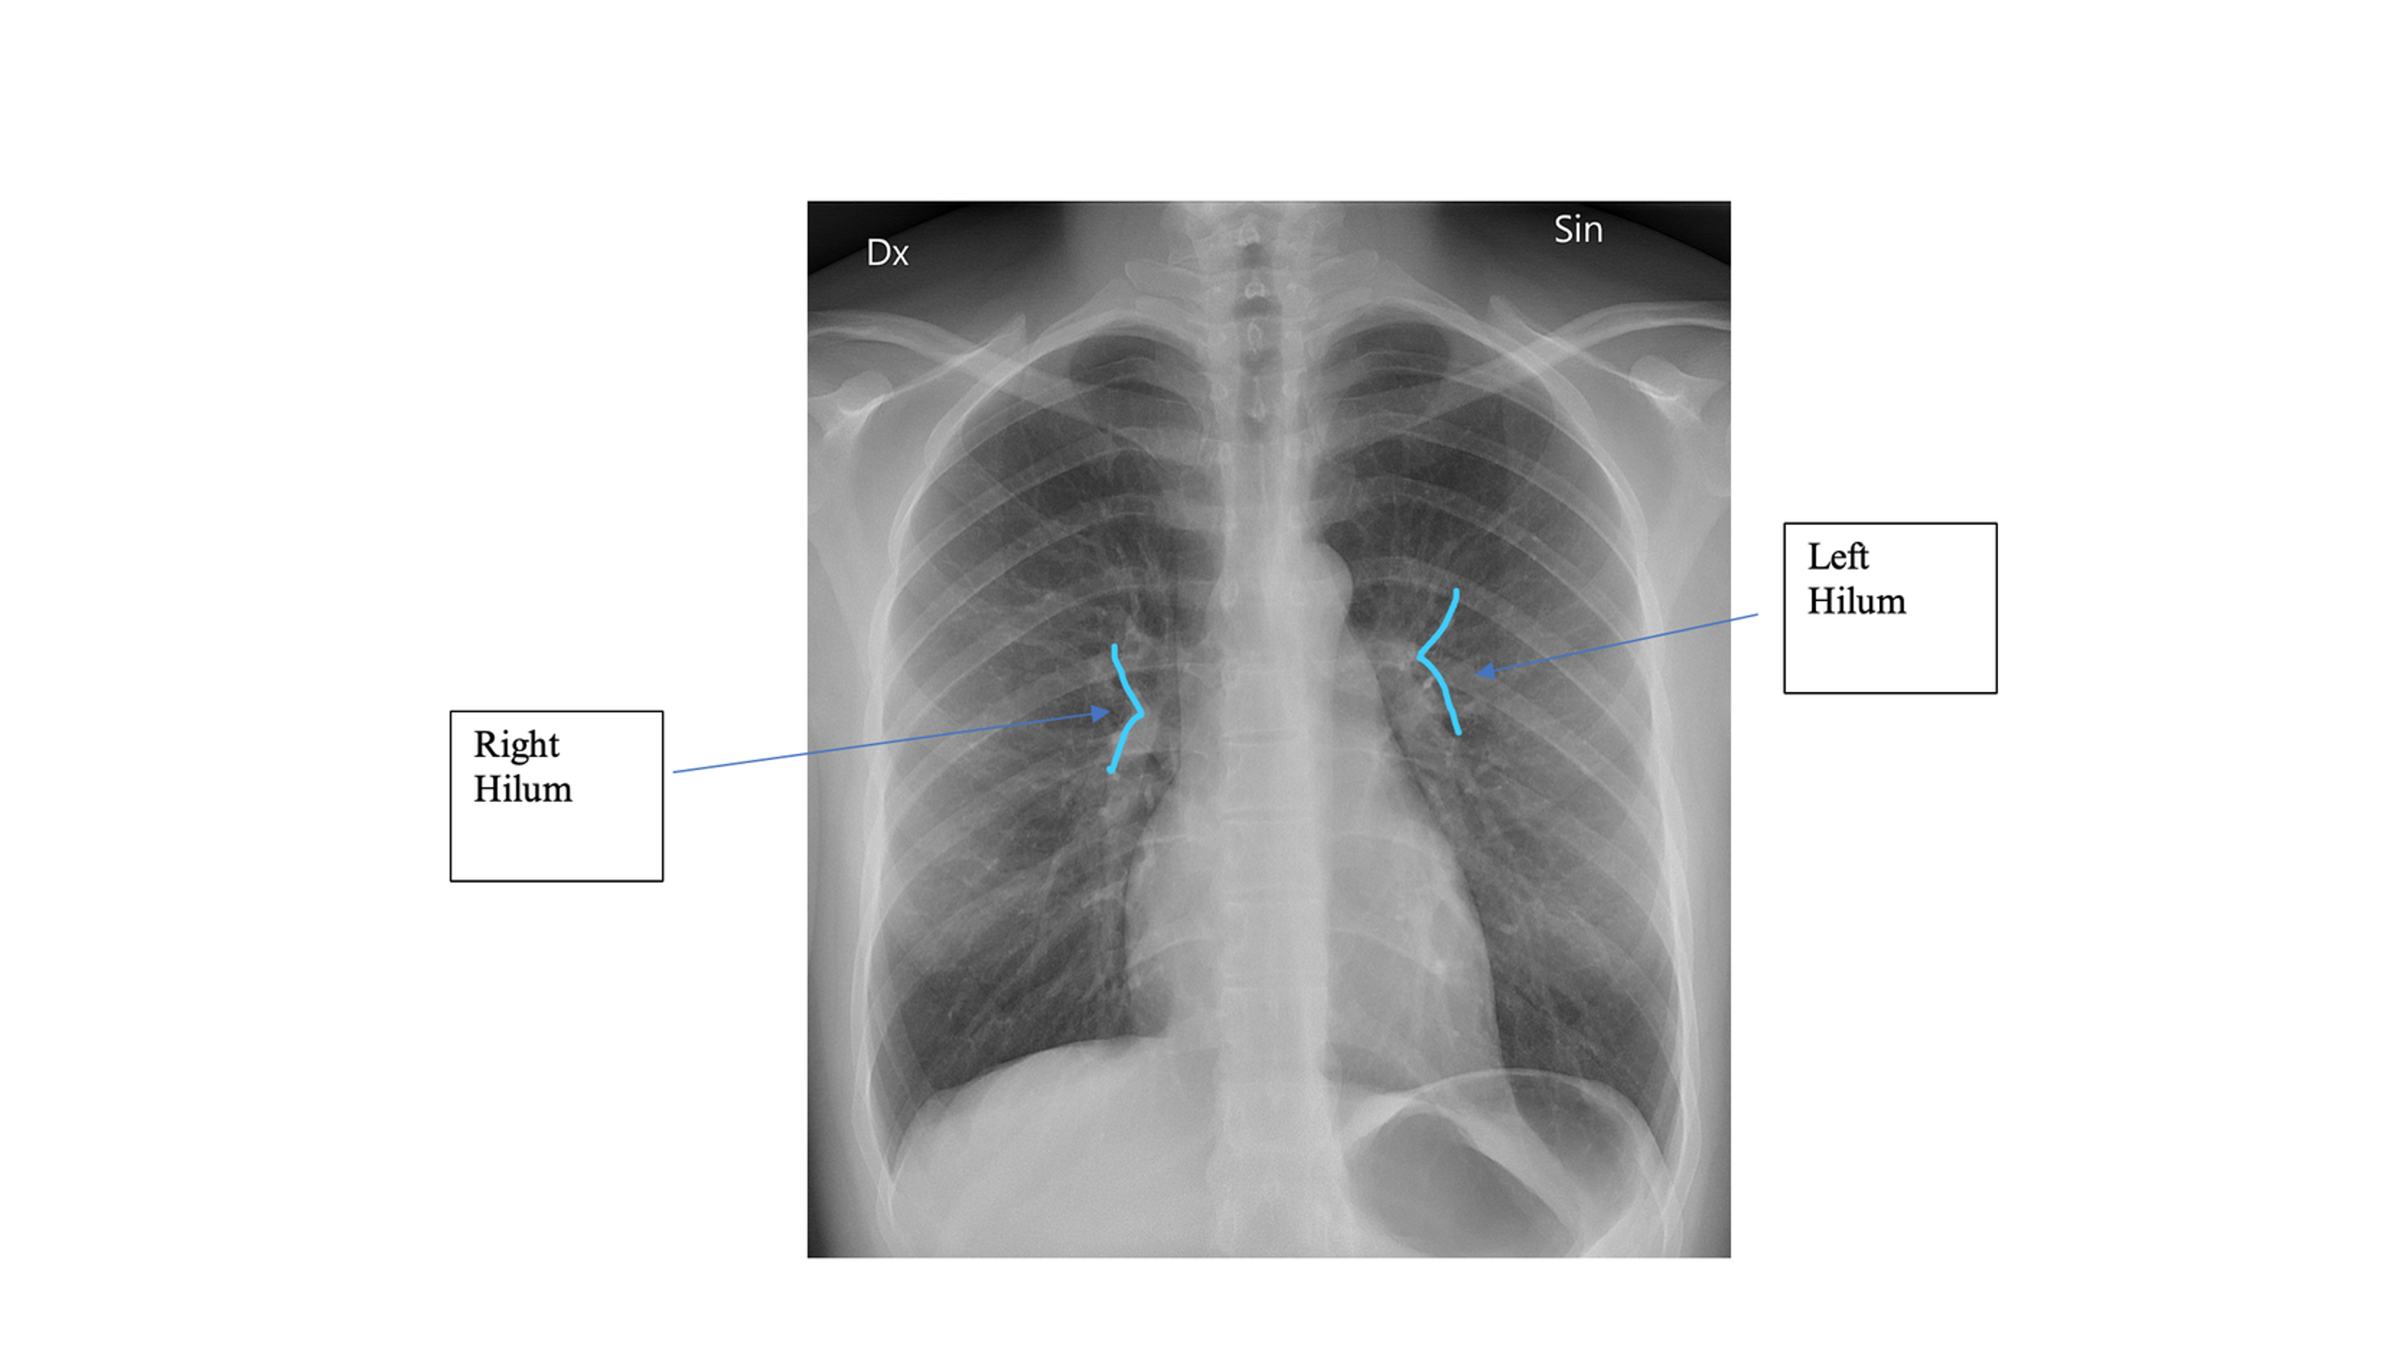

On CXR, the ___ hila should appear lower than the ___ hila

right hila appears lower than the left

On CXR, blurred vessels near hila may suggest infiltrates or fluid accumulation in what disease?

CHF

Airway Structures on CXR

Which lung hilum should appear higher on CXR?

Left hilum